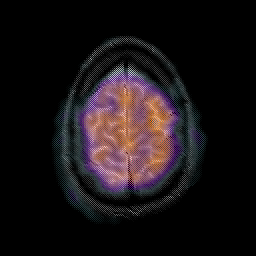

Glioma overlay -- Slice #24

[Home][Help][Clinical] Slice 24